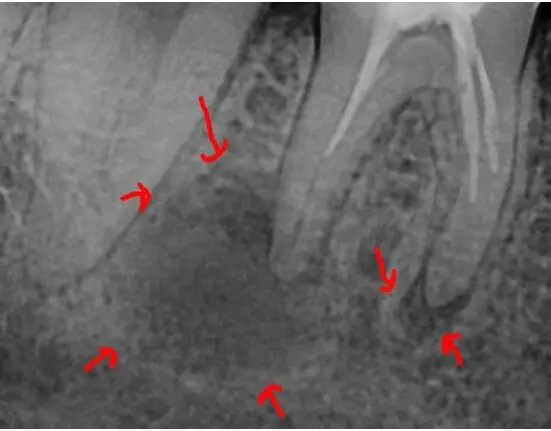

A patient came in with pain on tooth No. 30. It had a previous root canal performed. The pre-op radiograph showed inadequate cleaning, shaping, and obturation (Figure 1). In addition, there was a large lesion on the distal root and a smaller one on the mesial root (Figure 2). This prompted some questions.

| Figure 2. There was a large lesion on the distal root and a smaller lesion on the mesial root. | Figure 3. Endodontic treatment required two visits with calcium hydroxide for two weeks. |